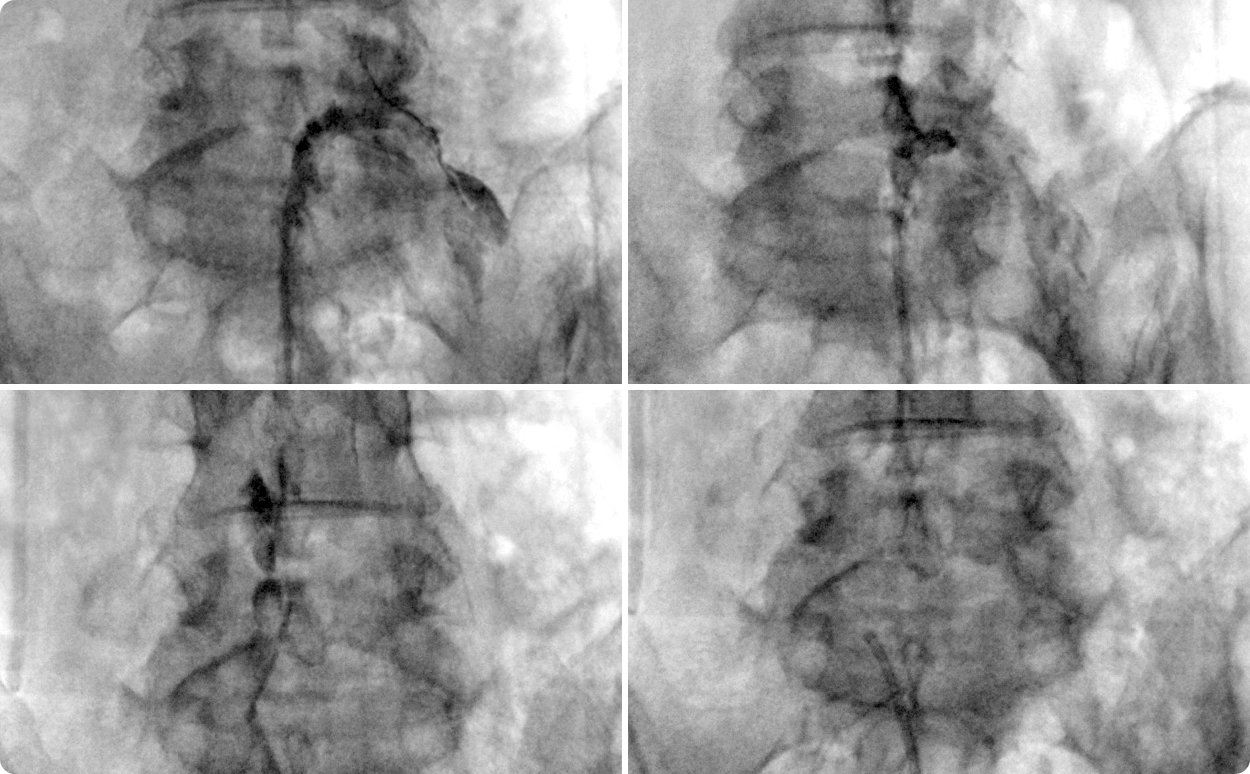

풍선확장 신경성형술은 허리디스크, 척추관협착증으로 인해 좁아진 척추관에 특수 카테터를 이용하며

풍선을 부풀려 치료하는 척추 비수술 치료 입니다.

풍선확장 신경성형술은 풍선을 이용하여 협착 부위를 충분히 확장시킨 후 협착 부위와 신경 사이의 유착을 녹이는 효소제와

통증의 원인이 되는 염증과 부종을 줄여주는 항염증제를 투여하므로 치료 효과가 더욱 높습니다.

C-Arm을 이용해 눈으로 확인하며 좁아진 척추관을 풍선확장 후

확장된 협착부위에 약물 투여

* 환자에게 받은 소중한 자료입니다.